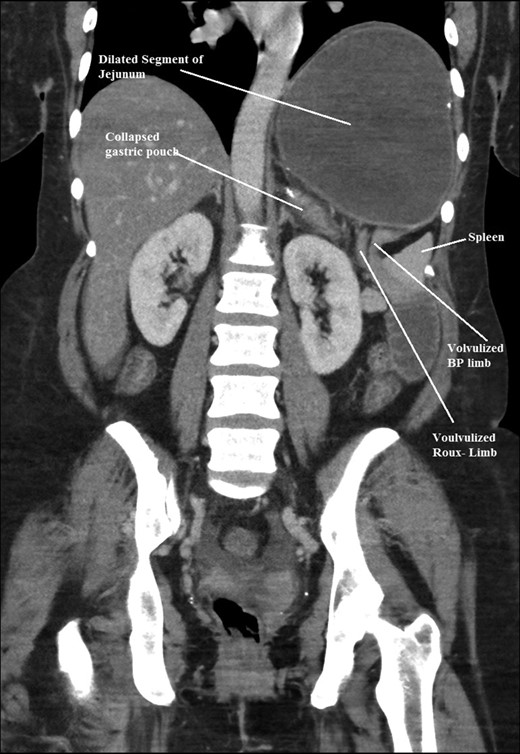

The intraoperative findings were not consistent with the radiological findings (Figs 1–4). As shown in the CT scan of abdomen and pelvis; multiple loops of dilated small bowel were seen, more predominantly dilated and matted bowel complex just above the spleen. The dilated bowel complex was decompressed using needle aspiration to help reduction of the bowel loops. The ileo cecal junction was then identified and traced back to the perisplenic hilar region. The trifurcation of three bowel loops (Roux limb, biliopancreatic limb and common limb) were identified with identification of ligament of Treitz. The prior gastric bypass was of ante colic- ante gastric type and Peterson’s defect was not closed. The above described bowel trifurcation had sunken postero- inferior to the spleen and had herniated through a potential space underneath the spleen and torsed around the splenic vessels and hilum. This picture was consistent with perisplenic small bowel volvulus. As noted earlier there was a massively dilated proximal small bowel segment above the spleen, displacing it caudally. Careful adhesiolysis was performed inferior to the spleen to release the segment of the trifurcation. The bowel segments once reduced were assessed and appeared viable. Of note, the spleen appeared better perfused after reduction. The remnant hernia defect of size 2 × 3 × 2.5 cm around the hilar region was then approximated using interrupted non-absorbable sutures. Enterotomy at the decompression site was closed with non absorbable suture. All potential sites of IH were re-examined and there was no evidence of any other internal herniation. Coelomic cavity was thoroughly irrigated and operation concluded successfully. Postoperative hospital stay was uneventful, and the patient was discharged home after two days.

Coronal CT scan of abdomen and pelvis showing volvulized bilio- pancreatic and Roux limbs within the obstructed segments in the splenic hilar region.